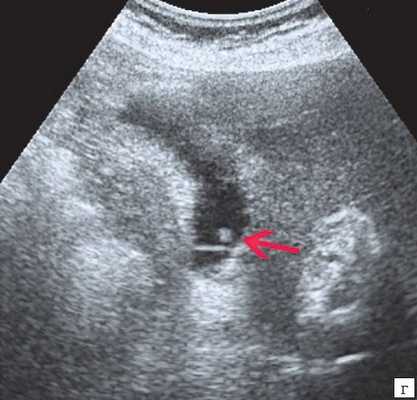

Рис. 4. Ультразвуковая картина опухоли головки ПЖ: образование в головке ПЖ (красная стрелка), расширенный панкреатический проток (зеленая стрелка).